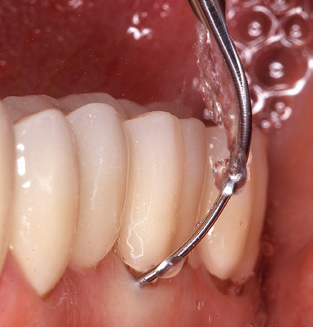

Das aktuelle Arbeitskonzept für die UPT

Als zentraler Bestandteil der UPT ist natürlich die Instrumentierung zum mechanischen Entfernen des Biofilms von vorrangiger Bedeutung. Der Ablaufplan einer UPT sieht zu diesem Zweck eine supra­, ggf. auch eine subgingivale Reinigung vor. Hier hat sich im Rahmen unseres Konzepts eine Kombination von Handinstrumenten und maschineller Reinigung bewährt. Für die maschinelle Vorgehensweise gibt es mehrere Optionen: Schallgeräte, Ultraschallgeräte sowie Pulverstrahlgeräte.

Die gute Ausleuchtung des Arbeitsfeldes stellt eine wesentliche Erleichterung dar. Bei dem von den Autoren genutzten System ist dies gelungen, indem ein 5­facher LED­Ring in das Handstück integriert wurde. Natürlich werden für dieses System unterschiedliche Arbeitsspitzen für die jeweiligen Indikationsbereiche angeboten. Eine gerade, universell einsetzbare Spitze ist das Basisinstrument zur maschinellen Instrumentierung natürlicher Zähne (Abb. 5a und b). Für schwer zugängliche Bereiche im Seitenzahnbereich werden gebogene Spitzen angeboten, die auch einen Zugang zu freiliegenden Furkationen ermöglichen (Abb. 6).